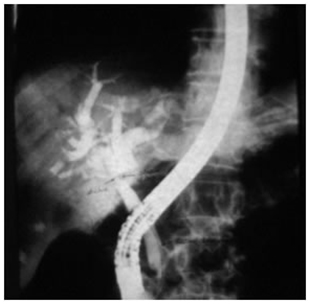

ERCP showing type I hilar block